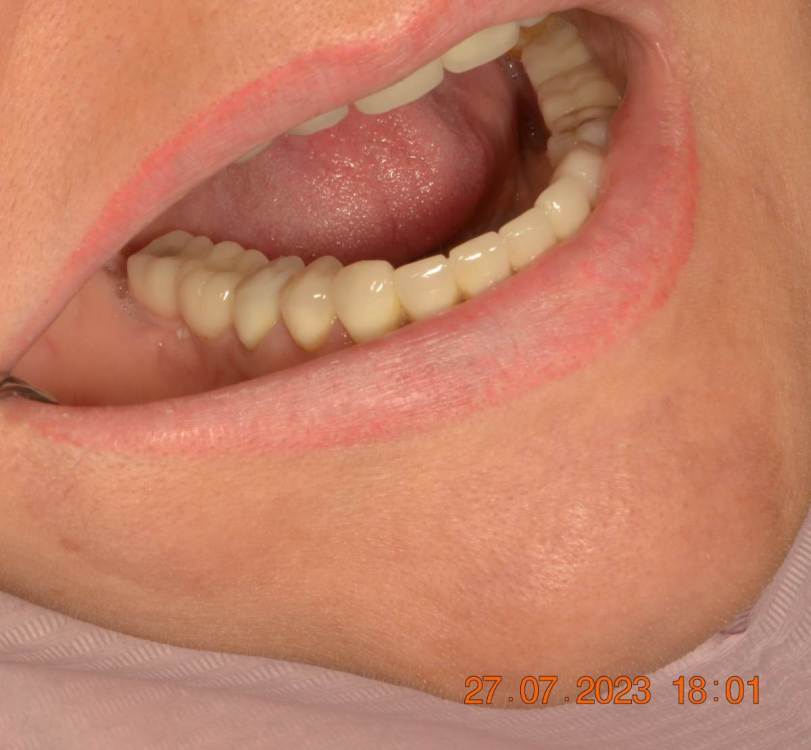

Большой Зеленый Опубликовано 15 августа, 2023 Поделиться Опубликовано 15 августа, 2023 Винтовая фиксация . 8 лет наблюдений .Полет нормальный. Немного прокрасились пломбы в шахтах. Пациентка довольна и счастлива. Привела уже вагон беззубых друзей и родственников. P/S. Система имплантов Ирис...:) 1 Ссылка на комментарий